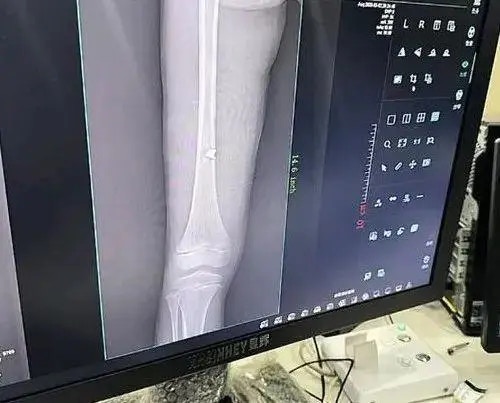

. w" U, {# W, v7 v* x& a) dos.tvboxnow.com彈片嵌入女孩腿骨。(南昌晚報)

彈片嵌入女孩腿骨。(南昌晚報)公仔箱論壇" A1 l ?# Q k) `3 q9 k

家屬看到女孩腿上流血,便帶女孩到醫院拍片,結果顯示孩子的左側股骨內側被彈片擊中。網民評論: